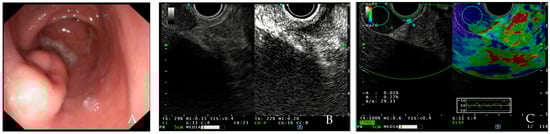

- Wu, J.; Zhuang, M.; Zhou, Y.; Zhan, X.; Xie, W. The value of contrast-enhanced harmonic endoscopic ultrasound in differential diagnosis and evaluation of malignant risk of gastrointestinal stromal tumors (<50 mm). Scand. J. Gastroenterol. 2022, 58, 542–548. [Google Scholar]

- Ignee, A.; Jenssen, C.; Hocke, M.; Dong, Y.; Wang, W.-P.; Cui, X.-W.; Woenckhaus, M.; Iordache, S.; Saftoiu, A.; Schuessler, G.; et al. Contrast-enhanced(endoscopic) ultrasound and endoscopic ultrasound elastography in gastrointestinal stromal tumors. Endosc. Ultrasound. 2017, 6, 55–60. [Google Scholar] [CrossRef]

- Tamura, T.; Kitano, M. Contrast Enhanced Endoscopic Ultrasound Imaging for Gastrointestinal Subepithelial Tumors. Clin. Endosc. 2019, 52, 306–313. [Google Scholar] [CrossRef]

- Pallio, S.; Crinò, S.F.; Maida, M.; Sinagra, E.; Tripodi, V.F.; Facciorusso, A.; Ofosu, A.; Conti Bellocchi, M.C.; Shahini, E.; Melita, G. Endoscopic Ultrasound Advanced Techniques for Diagnosis of Gastrointestinal Stromal Tumours. Cancers 2023, 15, 1285. [Google Scholar] [CrossRef]

- Yamashita, Y.; Kitano, M. Role of contrast-enhanced harmonic endoscopic ultrasonography (EUS) and EUS elastography in pancreatic lesions. Clin. Endosc. 2024, 57, 164–174. [Google Scholar] [CrossRef]

- Carrara, S.; Di Leo, M.; Grizzi, F.; Correale, L.; Rahal, D.; Anderloni, A.; Auriemma, F.; Fugazza, A.; Preatoni, P.; Maselli, R.; et al. EUS elastography (strain ratio) and fractal-based quantitative analysis for the diagnosis of solid pancreatic lesions. Gastrointest. Endosc. 2018, 87, 1464–1473. [Google Scholar] [CrossRef] [PubMed]